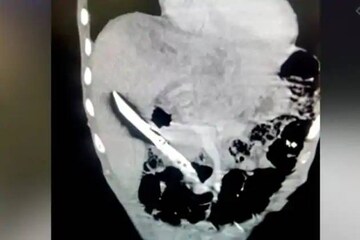

ന്യൂഡൽഹി: കടുത്ത വയറുവേദനയുമായി ആശുപത്രിയിലെത്തിച്ച യുവാവിന് ശസ്ത്രക്രിയ നടത്തിയ ഡോക്ടർമാർ ഞെട്ടി. 20 സെന്റീമീറ്റർ നീളമുള്ള കത്തി, യുവാവിന്റെ കരളിൽ തറഞ്ഞ നിലയിലായിരുന്നു. ഡൽഹി എയിംസിലായിരുന്നു സംഭവം.

ജൂലൈ 12 നാണ് വയറുവേദനയെ തുടർന്ന് യുവാവിനെ ആദ്യം സഫ്ദർജംഗ് ആശുപത്രിയിലേക്ക് കൊണ്ടുപോയത്. എന്നാൽ അവിടെ ആരോഗ്യസ്ഥിതി മോശമായതിനാൽ ജൂലൈ 19 ന് അദ്ദേഹത്തെ എയിംസിലേക്ക് മാറ്റുകയായിരുന്നു. വിശദമായ പരിശോധനയിലാണ് 20 സെന്റിമീറ്റർ നീളമുള്ള കത്തി കരളിൽ തറഞ്ഞിരിക്കുന്നതായി മനസിലായത്.

പിത്തസഞ്ചിക്കും ധമനിക്കും ഇടയിൽ കത്തി അപകടകരമായി കുടുങ്ങിയതായി എയിംസിലെ ഡോ. എൻ ആർ ദാസ് പറഞ്ഞു. അത്തരം സന്ദർഭങ്ങളിൽ, ശസ്ത്രക്രിയയിൽ സൂക്ഷ്മതയില്ലെങ്കിൽ അയോർട്ടയ്ക്ക് കേടുപാടുകൾ സംഭവിക്കുകയും കനത്ത രക്തസ്രാവം മൂലം രോഗി മരിക്കുകയും ചെയ്യും. അതിനാലാണ് ശസ്ത്രക്രിയ ഏറെ സങ്കീർണമായത്. ഡോക്ടർമാർ അന്നനാളം ഭിത്തി മുറിച്ച് കരളിൽ നിന്ന് കത്തി നീക്കം ചെയ്യുകയായിരുന്നു.